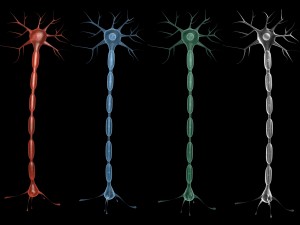

Neuron Sel Saraf Realistis Low-poly Model 3D

Neuron Sel Saraf Realistis Model 3D blend, png, Dari 3dcreations

A highly detailed and realistic 3D model of a human nerve cell (neuron), showcasing dendrites, axon, and synaptic terminals with scientific accuracy. Perfect for anatomy study, educational visualization, and medical simulations.

⚙️ Key Features:

Realistic and scientifically accurate nerve structure

Includes detailed axon, dendrites, and cell body

Ideal for educational and medical 3D projects

Smooth mesh topology for easy rendering and animation

Suitable for VR, AR, and scientific visualization

High-quality texture and proportionally accurate modeling